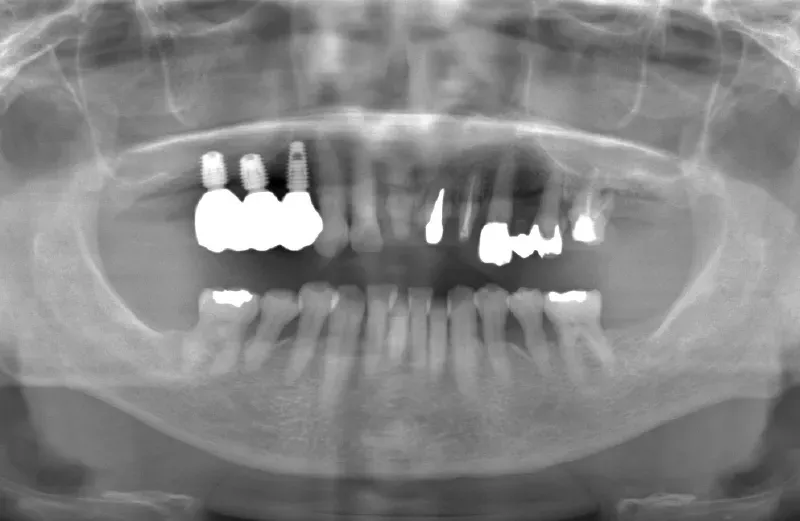

メガジェンオペ症例

メガジェンオペの症例紹介01

治療前

治療後

| 主訴 | 上入れ歯は以前に入れたことがあるが違和感が強く入れられなかったのでインプラントで治療して欲しい。 他院では上顎洞までの垂直骨量が1~3mm程度しかないのでサイナスリフトが必須であり、インプラント治療で歯が入るまでに1年以上かかると言われたのでセカンドオピニオンを希望で来院。 |

|---|---|

| 治療期間 | 2.5ヶ月で仮歯が入り、 4ヶ月で最終補綴物が入って終了。 |

| 費用 | 約1,500,000円 |

| 治療内容 | エクストラワイドショートインプラントを埋入し、上顎洞を移植材を用いずに挙上しインプラントを埋入した。約2.5ヶ月で仮歯を装着し、様々な機能面に問題がないことを確認し4ヶ月で最終補綴物を装着して終了した。 |

| 治療のリスク | インプラント埋入オペ時に術者が上顎洞内にインプラントを迷入させる可能性がある。これは術者が技術的に熟練していれば防ぐことが可能。 |